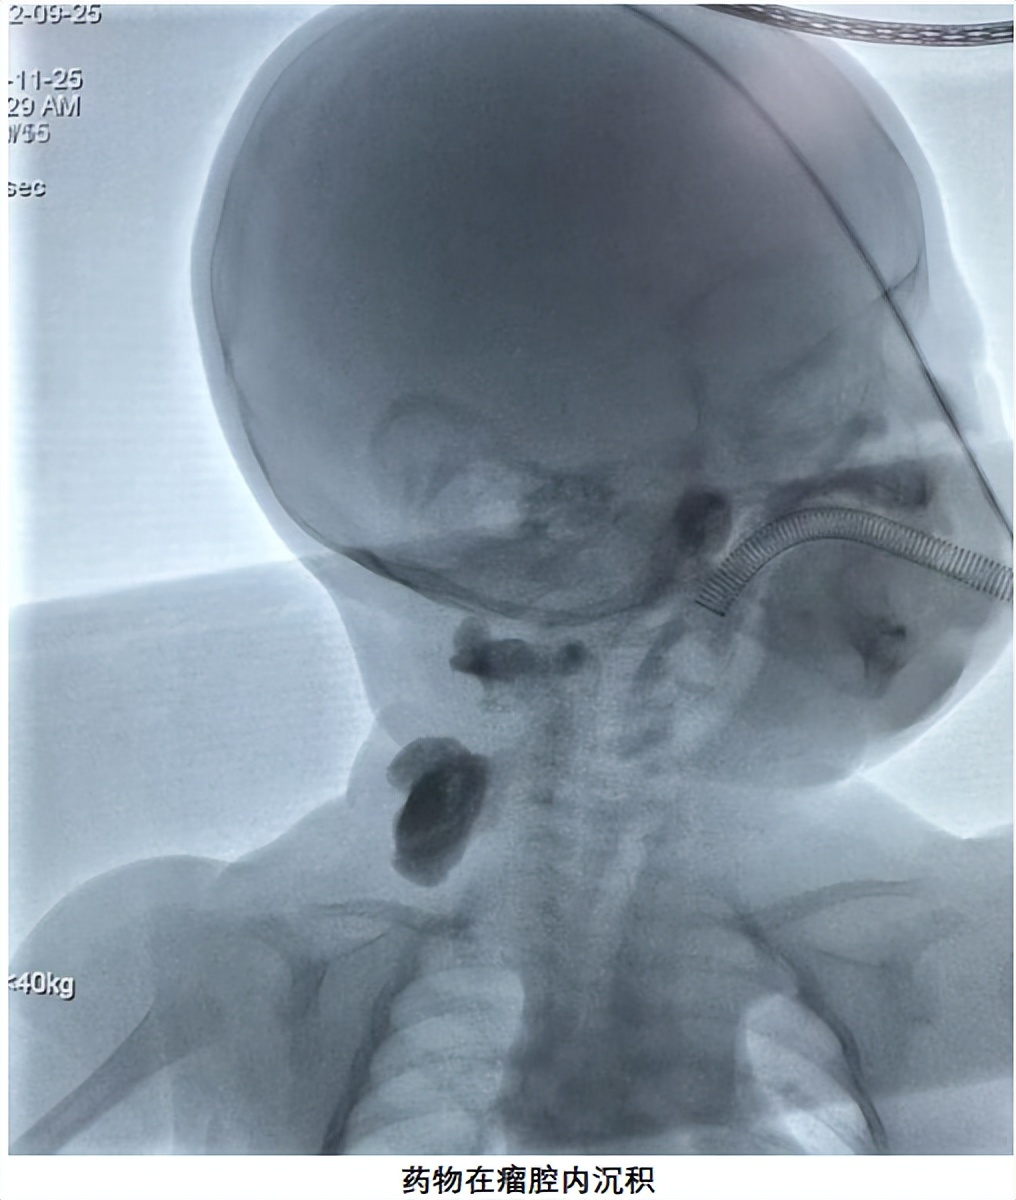

【推荐理由】该病例为多发淋巴管瘤,需要积极处理,本患儿采用局部硬化治疗,效果明显。

患儿为2月男婴,家长孕期产检就发现患儿左肩至腋下、左手等部位多发肿物,家长非常焦虑,不知道这是什么病,对治疗方案也一无所知,我看过患儿后,一边详细了解孩子病情和检查,一边安慰父母,告知父母这属于淋巴管瘤,但本患儿情况特殊,因瘤体较大,可能会对气道造成压迫,所以需要尽早进行干预,目前多采用介入微创治疗,淋巴管瘤属于我们科室的常见病,我们已经治愈很多类似的患儿,告诉家长不要太担心,并给家长看了类似病人的成功治疗的案例照片。家长很快平静下来,也决心在这里完成手术。

在安排的手术时间,家长如约住院,顺利完成术前准备,手术当天,患儿在全麻的过程中完成了手术,手术仅耗时半小时,术中无出血,手术过程非常顺利,术后孩子也没有任何不适,身上也没有任何伤疤。共住院3天,患儿平稳出院。